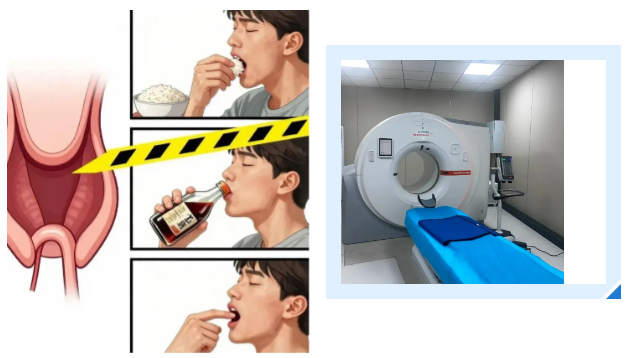

吕主任借此案例提醒广大市民,鱼刺卡喉后,千万不要抱有侥幸心理,更不要尝试吞米饭、喝醋、用手指抠喉咙等土办法。这些方法不仅无法取出鱼刺,还可能导致鱼刺越扎越深,引发食道穿孔、感染、大出血等严重并发症,甚至危及生命。

正确的做法是:立即停止进食,尽量减少吞咽动作,避免鱼刺移位。如果能看到鱼刺,可以用消毒镊子轻轻取出;如果看不到鱼刺或取出困难,应第一时间前往医院就诊,通过喉镜、胃镜、CT等检查明确鱼刺位置,由专业医生进行处理。

接诊的吕主任详细询问了陈女士的情况,结合她持续加重的咽痛,判断事情没那么简单。立即安排她进行双源CT检查并辅以三维重建技术。检查结果让所有人都捏了一把汗:一根近3公分长的鱼刺,深深卡在食管入口处,不仅位置刁钻,还已经刺穿食道,周围创面出现感染。